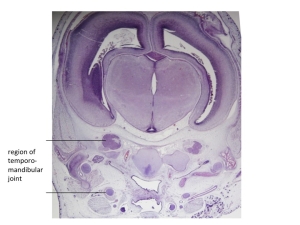

Stage 23

CfS 23

d41-44